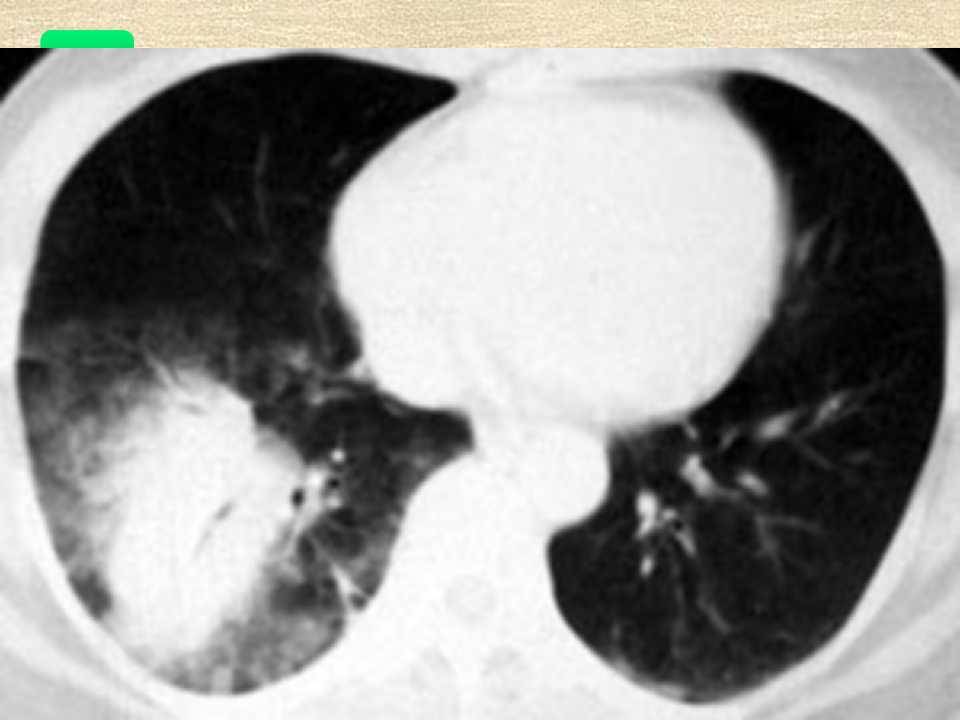

肺癌影像学表现